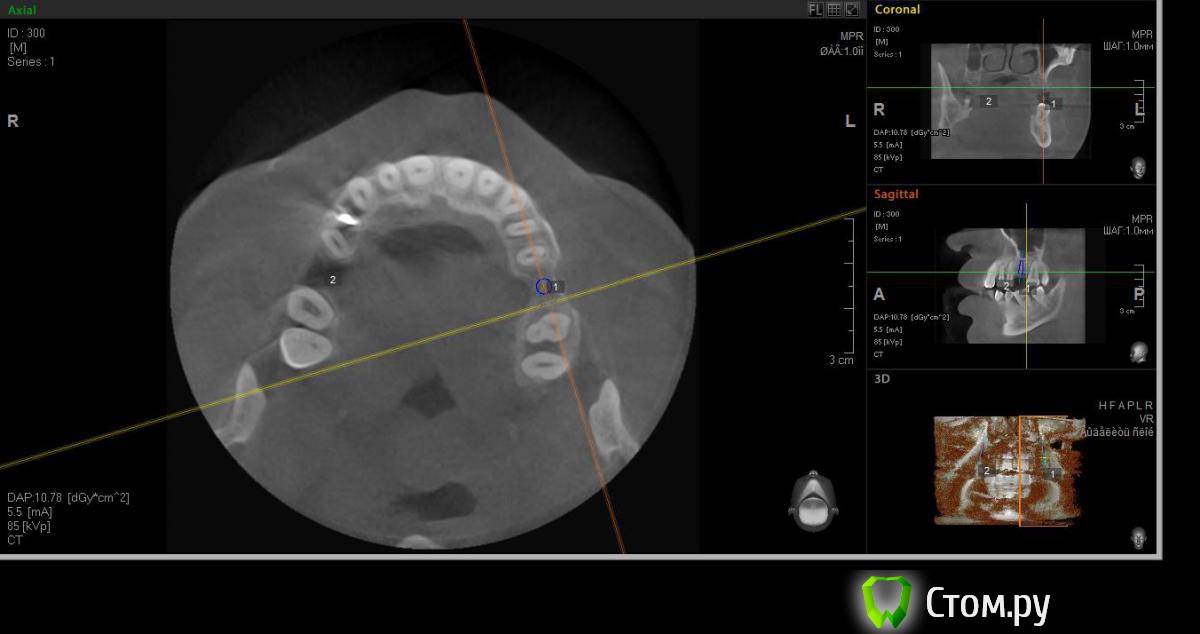

faity Опубликовано 18 мая, 2014 Автор Поделиться Опубликовано 18 мая, 2014 хочу вот так сделать, на 1.6 мягкий лифт, в обл 2.6 не лезтьвинты Ankylos 1.6- 4,5/11 2.6- 3,5/9,5кости в области 1.6- 7,5мм, должно хватить для закрытого, открытый пациент не потянет по финансам.какие мысли? Ссылка на комментарий

red_butler Опубликовано 19 мая, 2014 Поделиться Опубликовано 19 мая, 2014 Я бы не планировал хирургию исходя из финансовых пожеланий пациента, и 1.6 вел бы с открытым синусом. Представьте что при закрытом порвали мембрану, открытый придется делать, и за свой счет. Винт в позицию 1.6 поставил бы меньшего диаметра Ссылка на комментарий

faity Опубликовано 19 мая, 2014 Автор Поделиться Опубликовано 19 мая, 2014 значит буду открытый делать, и винт на 3,5а по поводу 2.6 предложений никаких? Ссылка на комментарий

faity Опубликовано 19 мая, 2014 Автор Поделиться Опубликовано 19 мая, 2014 Я бы не планировал хирургию исходя из финансовых пожеланий пациента, и 1.6 вел бы с открытым синусом. Представьте что при закрытом порвали мембрану, открытый придется делать, и за свой счет. Винт в позицию 1.6 поставил бы меньшего диаметрапоменял винты на 3,5/11 Ссылка на комментарий

red_butler Опубликовано 19 мая, 2014 Поделиться Опубликовано 19 мая, 2014 (изменено) Не знаю диаметры винтов в этой системе, между 3.5 и 4.5 Промежуточного нет?А 2.6 без синуса и диаметр больше Изменено 19 мая, 2014 пользователем red_butler Ссылка на комментарий

faity Опубликовано 19 мая, 2014 Автор Поделиться Опубликовано 19 мая, 2014 Не знаю диаметры винтов в этой системе, между 3.5 и 4.5 Промежуточного нет?А 2.6 без синуса и диаметр большепромежуточных к сожалению нета 2,6 больше не получитсяэто при ныненшнем радиусе и положении, если делать больше винт, то больше углублять, а тогда в синус провалюсь Ссылка на комментарий